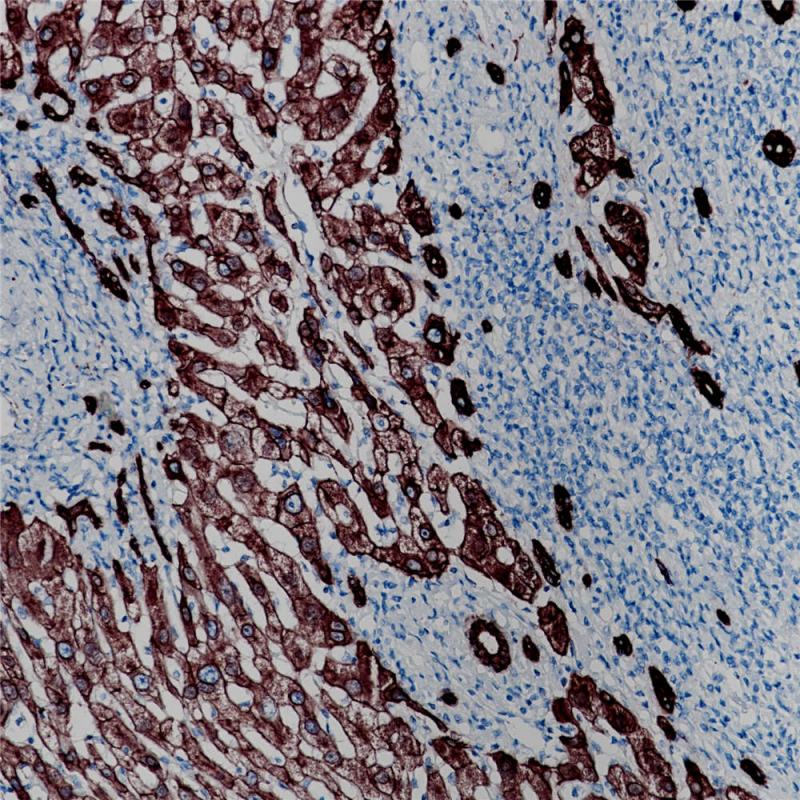

CK18(细胞角蛋白18,也叫角蛋白18)是一种I型细胞角蛋白。CK18和其II型配对的CK8可能是中间纤维基因家族中最常见的产物。在一些上皮细胞类型中,CK8和CK18是唯一存在的角质蛋白。经典的例子就是肝脏,CK8/CK18是正常肝细胞中仅有的一对角蛋白,代表了肝脏的特征。对于其他高度专化的薄壁组织上皮细胞,如胰腺的腺泡细胞、肾脏的近端管状上皮细胞,以及某些内分泌细胞如胰岛细胞,也是如此。此外,CK8/CK18与其他角化蛋白一起出现在各种假复层(如呼吸)和复杂(如腺体)上皮以及膀胱上皮。即使在非角质化的复层鳞状上皮细胞中,CK8、CK18以及CK19和基本复层上皮角化蛋白也可以在基底细胞层中集中表达。在恶性肿瘤方面,除了一些分化的鳞状细胞癌,CK8和CK18在大多数癌症中都表达。因此,CK8和CK18抗体对大多数腺癌、肝细胞癌、肾细胞癌和神经内分泌癌有明显染色效果。